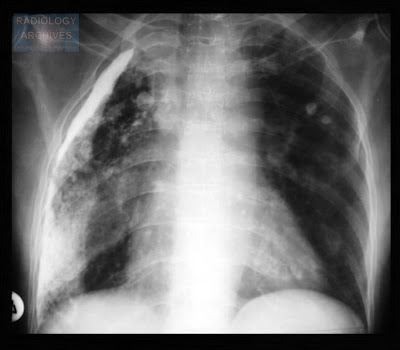

Εικόνα 2, ουραιμική πλευρίτις. Σταδιακή λύση, μετά την εφαρμογή περιονοαϊκής διαλύσεως.

Αυτόματη λύση ουραιμικής πλευρίτιδας τυπικά αναμένεται σε διάστημα 4-6 εβδομάδων, που καταλείπει κλινικά ενδιαφέρουσα ινώδη πάχυνση του υπεζωκότος,, στους περισσότερους ασθενείς. Σε σποραδικές περιπτώσεις αναπτύσσεται ένα ζελατινώδους υφής πλευριτικό εξίδρωμα, που απολήγει στην ανάπτυξη σκληρής παχυπλευρίτιδας.